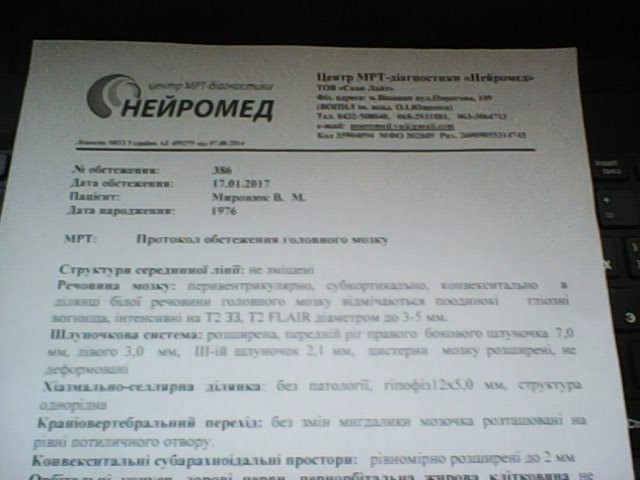

МРТ головного мозга: Расшифровка снимков и Интерпретация

Раздел: Визуальные уроки